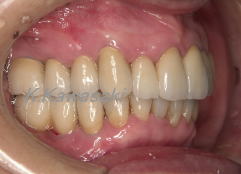

型採り→被せ物の装着

歯形をとりセラミックの歯を装着しました。機能的、審美的にも満足していただきました。

口元もスッキリして素敵な笑顔になりました。 |